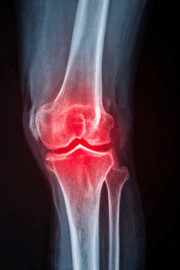

How to Keep Your Knees Healthy for Life

Your Knees Do a Lot for You From walking and climbing stairs to running, dancing, or kneeling in the garden, your knees are involved in almost every lower body movement you make. They’re built to be strong and resilient — but like any joint, they need the right care to stay healthy for the long… Read More